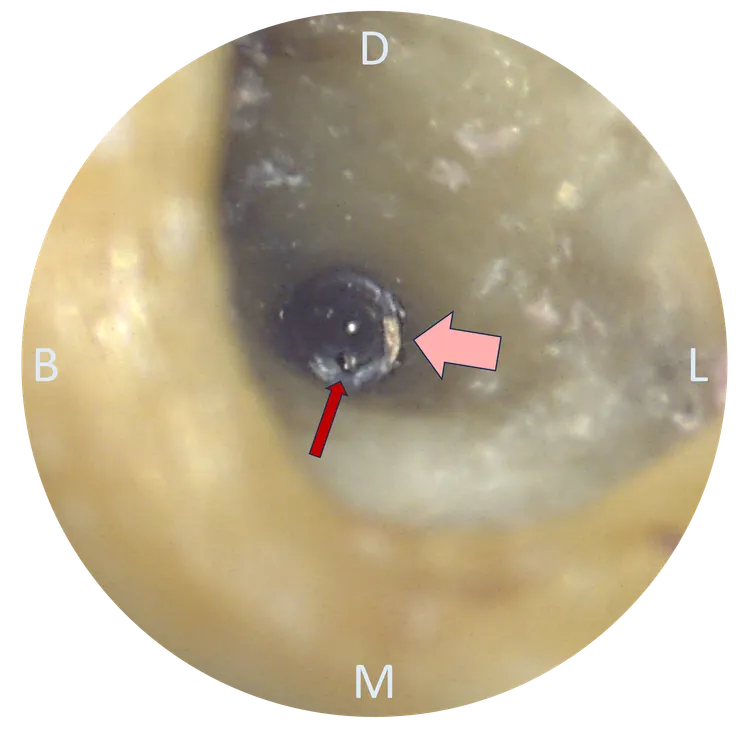

不光是 PA film, 在 CBCT 上我們也可以依據 root form 推測出 canal 的走向 (如下排圖中的紅色標示處)。於是我們可以清楚地看出,先前的路徑 (粉紅色箭頭標示處) 明顯地往 lingual & mesial 偏移,並勘勘在 perforation 前停住......

所以真正的路徑應該會是在舊充填的 DB side.

把 CBCT 的資訊記在腦中後,我們轉移到顯微鏡下來看看實際的情況:

把舊 GP 大致移除後,幸運地在根管壁上看到一個突兀的洞 (紅色箭頭所指),剛好就位於原本路徑 (粉紅色箭頭) 的 DB side !